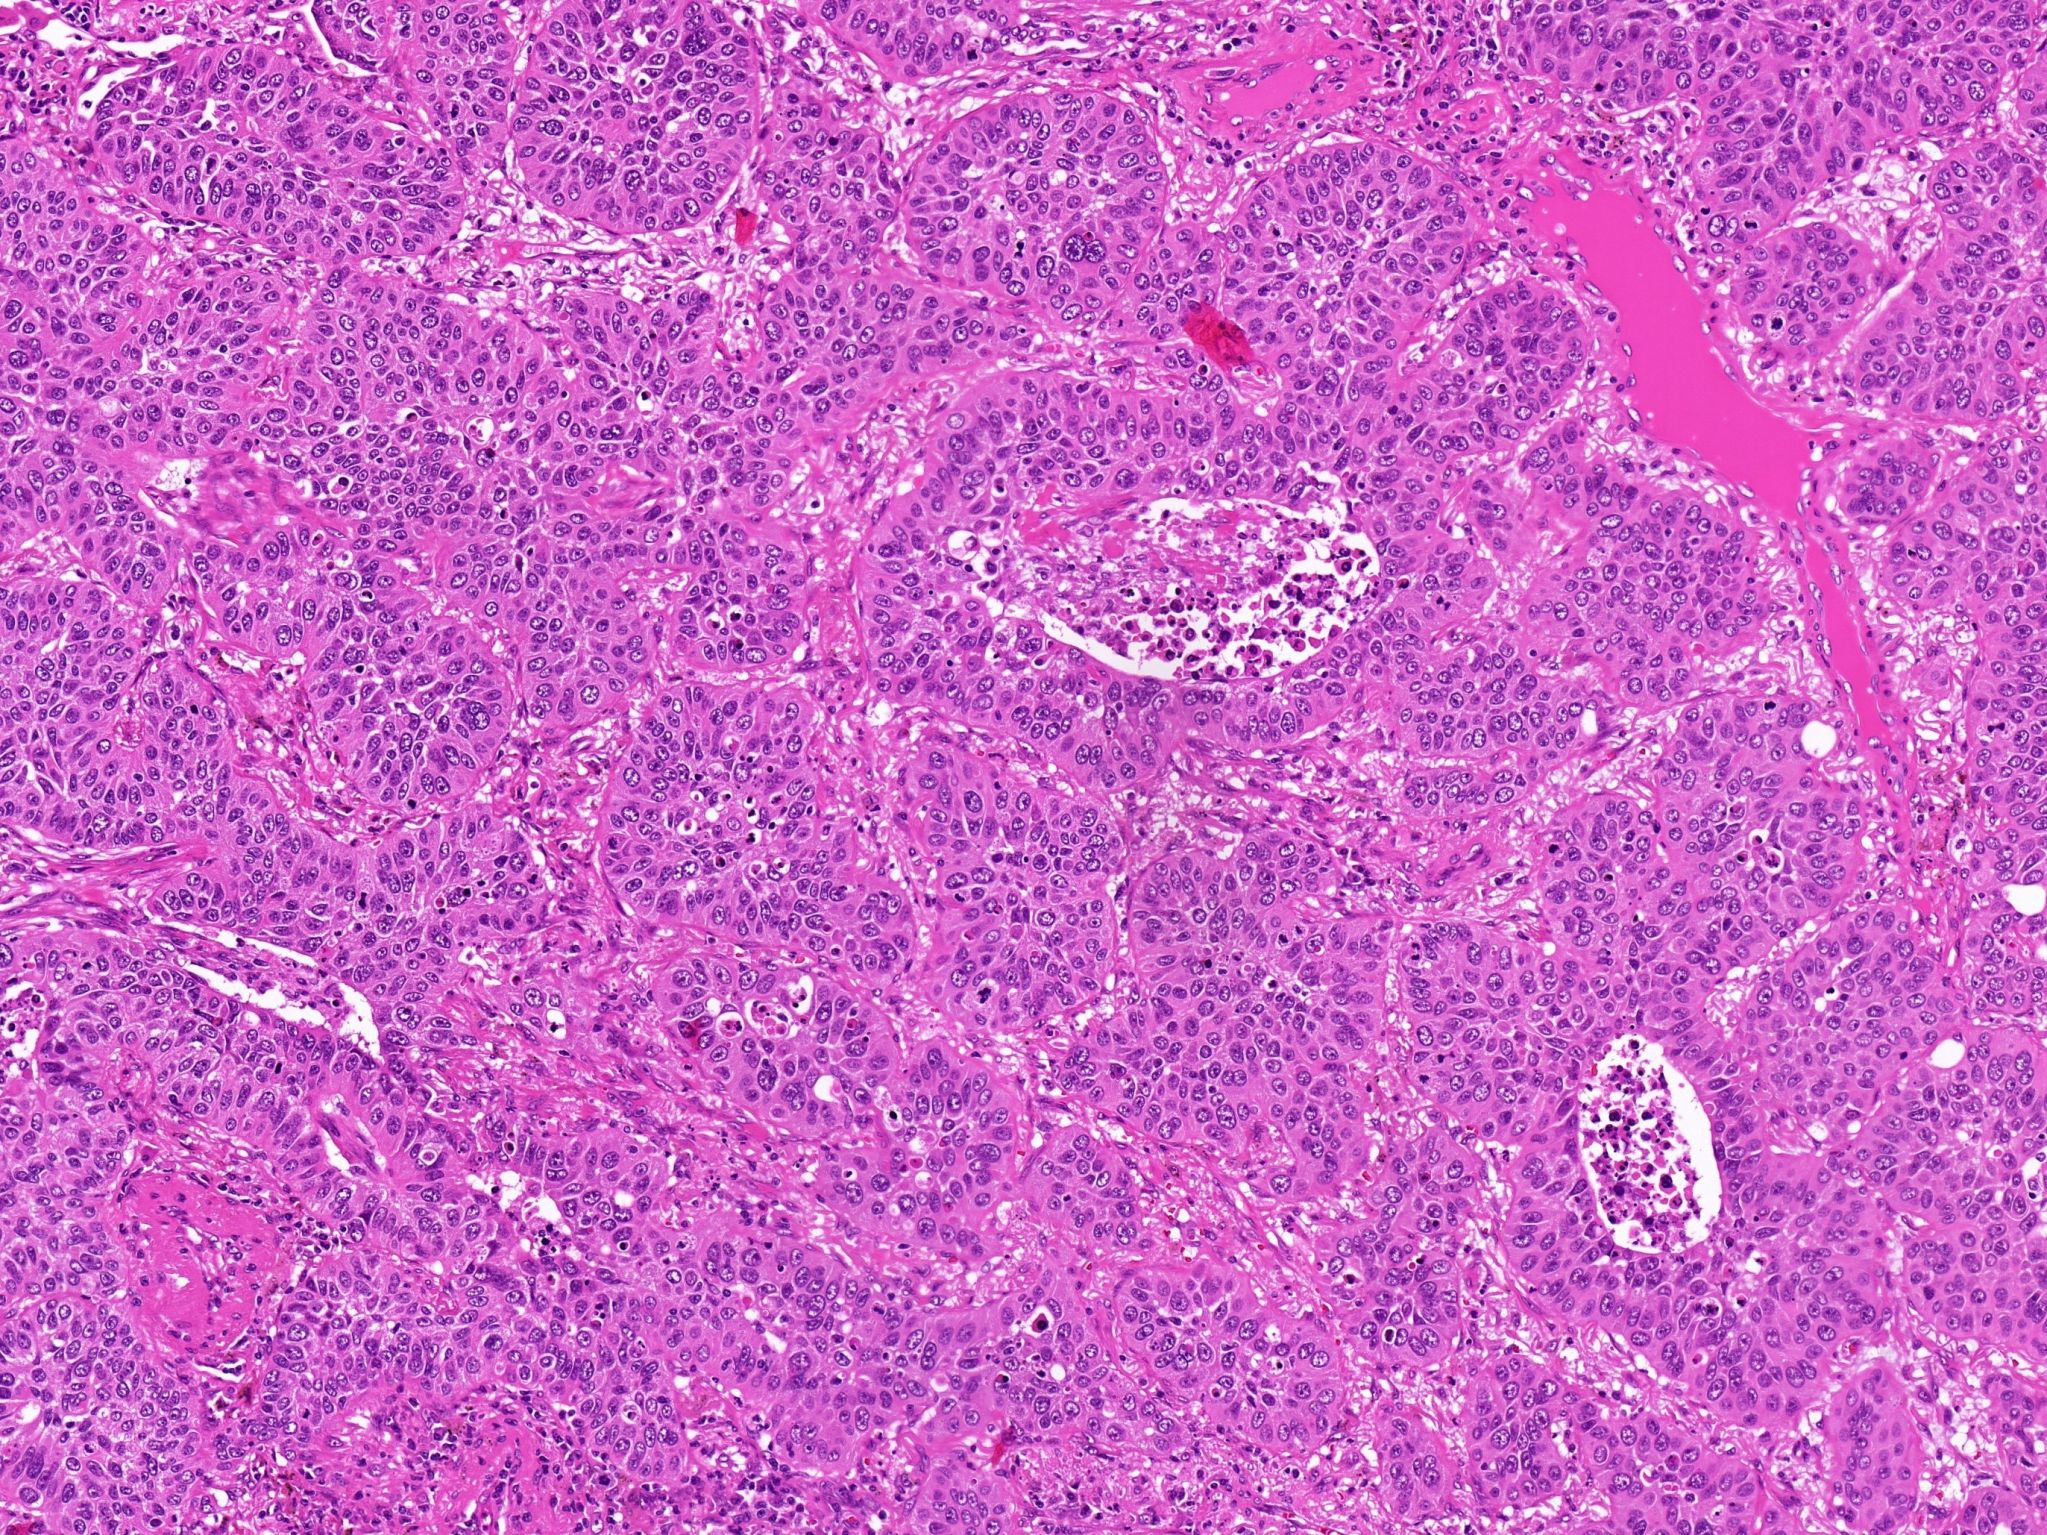

Histologisches Schnittpräparat eines primären Lungenkarzinoms. Foto: Jurmeister/Charité